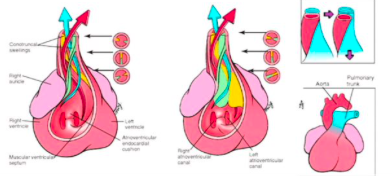

how is the conotruncal septum formed?

the conotruncal swellings that form the conotruncal septum rely in the migration of neural crest cells from the neural tube

What can abnormal neural crest cell development or migration cause?

a number of defects in septation of the truncus arteriosus into pulmonary trunk and aorta

Name 3 septation defects of the truncus arteriosus

What is a persistant truncus arteriosus?

What is transposition of great vessels?

What is the tetralogy of fallot?

4 abnormalities caused by the same primary deect

What is the underlying cause of tetralogy of fallot?

Unequal division of the truncus arteriosus caused by anterior displacement of the aorticopulmonary septum